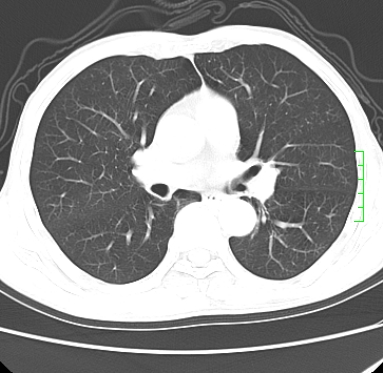

m,73y。膝关节疼痛伴双下肢水肿。入院常规胸片发现结节灶。增强为静脉期。

浅分叶、棘突,考虑右下肺周围型肺癌

考虑周围型肺癌  ,双上肺结核。

肿块周围可见局限性气肿,考虑肺癌可能性大。双肺上叶继发型肺结核。

指套征,强化明显,近侧肺组织局限性肺气肿,考虑支气管类癌,慢支、肺气肿、双上陈旧性tb、冠脉钙化。

鉴别:先天性支气管闭锁,变态反应性支气管肺曲霉菌病,肺癌,支气管囊肿,支扩黏液嵌塞。

1)考虑右肺下叶周围型肺癌。2)右肺上叶及左肺感染性病变(结核可能)。3)肺气肿。4)冠状动脉钙化。